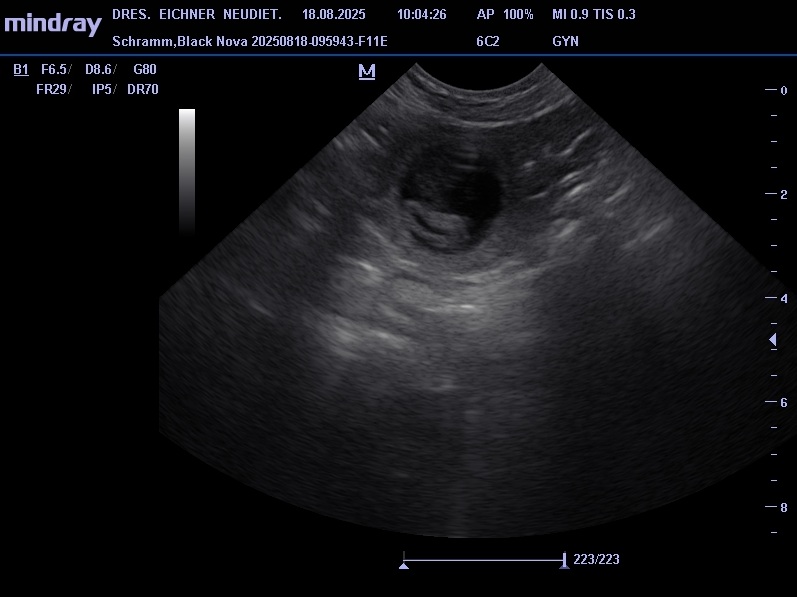

Unsere jüngsten Hündin Black Nova hatte ihr erstes Date mit Pepe am 19. 07. 2025. Pepe ist ein kräftiger kompakter Rüde mit sehr guten Gesundheitswerten. Die zwei haben sich beim Date und auch schon bei einem vorhergehenden Treffen gleich verstanden. Am 18.07. waren wir dann beim Ultraschall, das Ergebnis war positiv, somit erwarten wir Mitte September kleine Bullis in unseren Kennel. In der Nacht vom 20. zum 21. 09. 2025 sind 7 kleine Apfelknirpse bei uns gelandet, 4 Rüden und 3 Hündinnen. Nova und den Welpen geht es gut alle sind wohlauf. Alle Knirpse haben ihr Zuhause gefunden und sind ausgezogen.